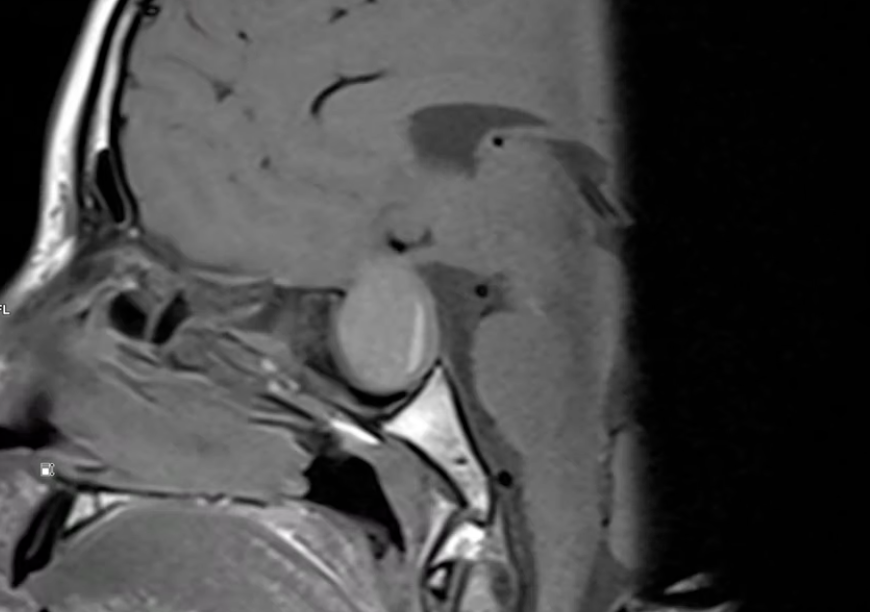

Video 1: sag T1

Discuţie caz nr 84: diagnosticul de trimitere a fost suspiciune de formațiune tumorală suprasellară pacientul prezentând simptome datorate compresiei nervilor optici; se evidențiază o leziune ovalara net delimitată dezvoltată la nivelul șeii turcice cu evoluție suprasellara ce are conținut spontan în hipersemnal T1 cu nivel fluid-fluid și cu priză de contrast la nivelul peretelui subțire. Leziunea are efect de masă asupra structurilor de vecinătate deplasând segmentele distale ale nervilor optici spre lateral și superior și chiasma optică spre superior.